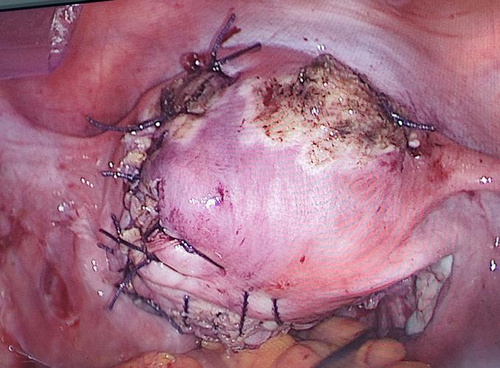

治疗多发性子宫肌瘤的方法,主要有期待观察、药物治疗、手术治疗这几种,手术治疗又分为传统的开腹子宫肌瘤剔除术、腹腔镜手术、聚焦超声手术等几种方式。